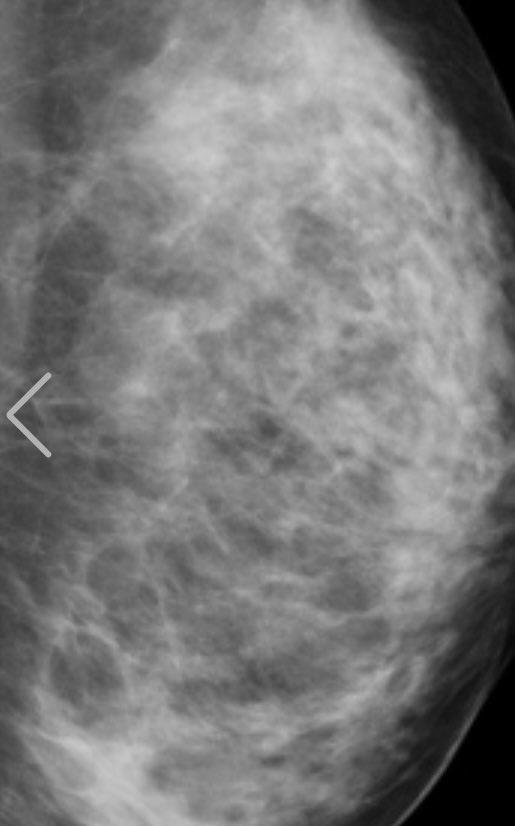

タレント、女優の鈴木ふみ奈(32)が14日、胸部レントゲン写真をツイッターに投稿した。

人間ドックを受診した際のもので、「私の胸部レントゲン!笑」の文言とともに正面・左右から撮影したものなど4枚を掲載。「これで私の胸が天然な事は証明できたのかな?」と〝加工なし〟を強調した。